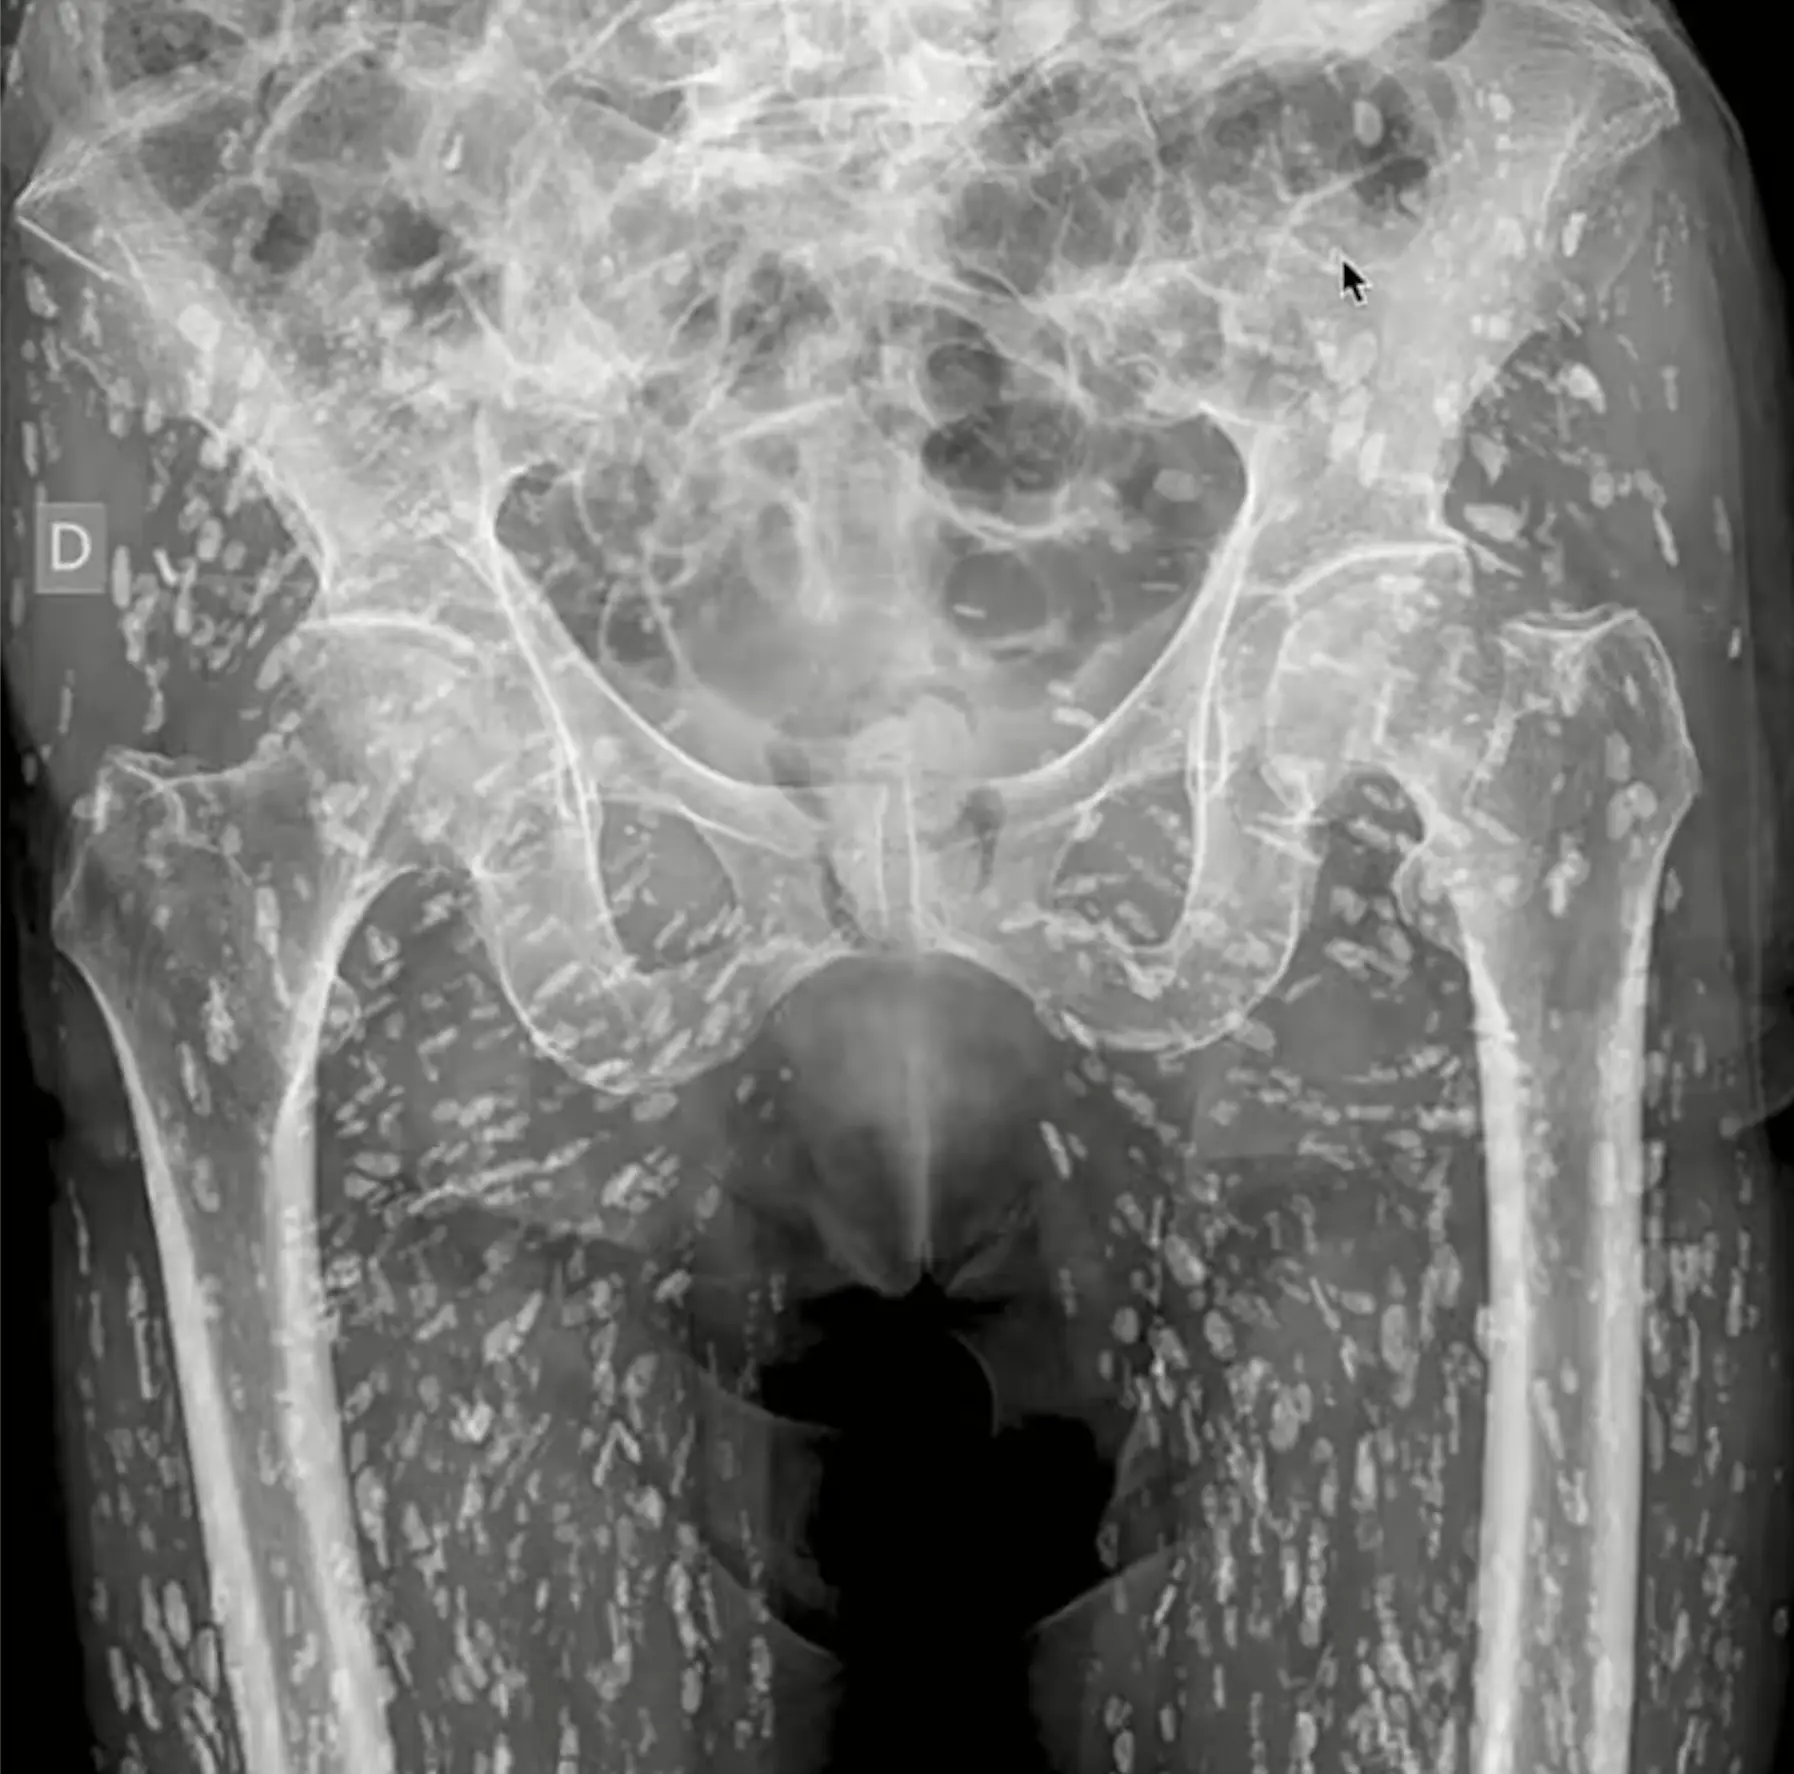

A disturbing X-ray has been shared on social media, showing what a body infested with tapeworms looks like.

Sam Ghali, of the University of Florida, uploaded the photo on X, calling it one of the 'most insane X-rays I’ve ever seen'.

"These cysts can travel anywhere throughout the entire body, heavily to the muscular and soft tissue of the hips and the legs," Ghali said.

"If just in the pelvis, they don’t pose a life-threatening problem.

"The problem is if they travel to the brain and lodge there.

"That can cause very serious issues. As you can imagine, that can lead to neurological symptoms like headaches, confusion, seizures and even death."